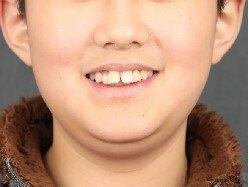

治疗前

11岁小男孩,主诉龅牙,牙齿不整齐。

检查:侧貌突,开唇露齿。上颌前突,下颌后缩,上前牙前突10mm左右,咬合深,咬至上颌粘膜,上下牙弓狭窄,牙列拥挤不齐。